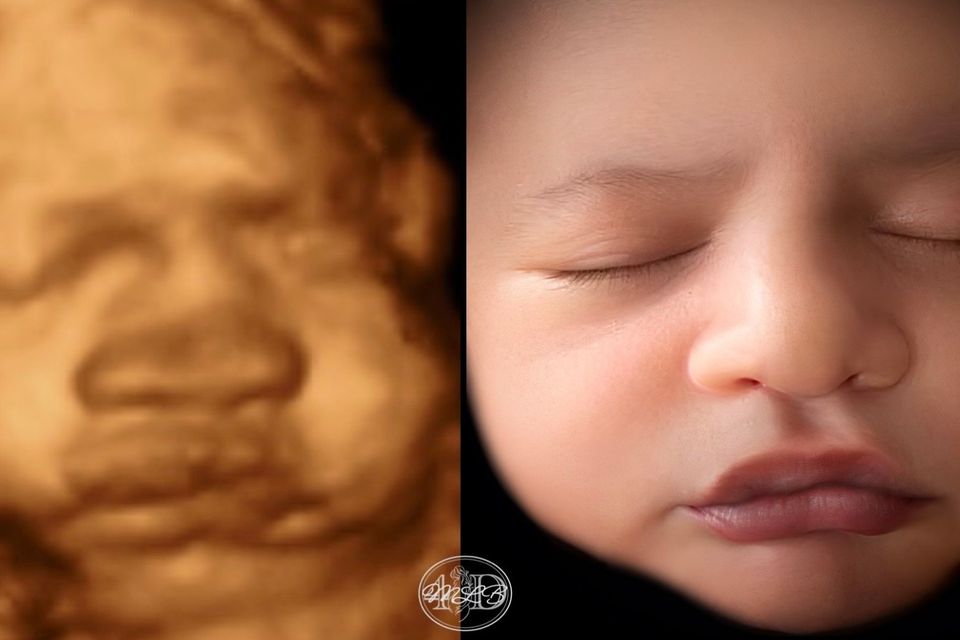

Most Realistic & lifelike photo you can get until the arrival of your little one. Using the newest technology to change your 3d/4d photo into something more realistic without changing any of your baby's features.